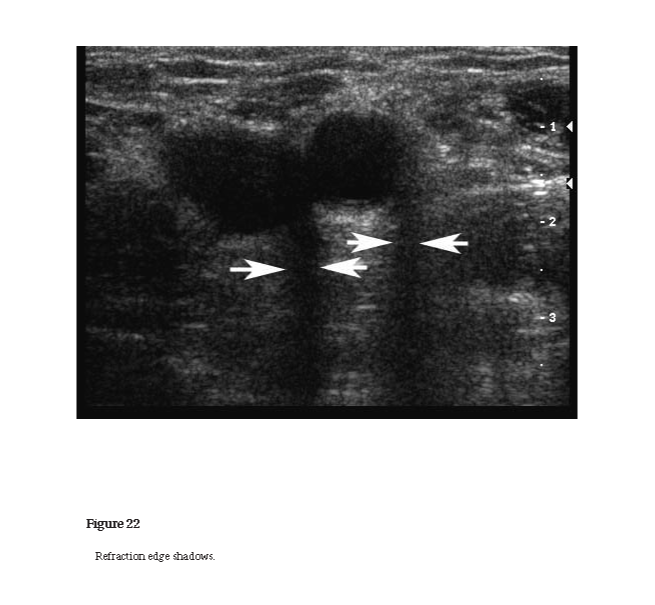

The change of direction of propagation of a sound wave when it passes from one medium to another in which the sound speed is different or when there is spatial variation in a medium’s sound speed (see Figures 6 and 22).